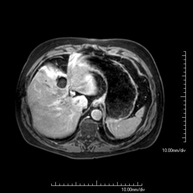

- Abdomen MRI

This non-invasive diagnostic procedure uses an electromagnetic field and radio waves (from a transmitter and receiver) to acquire high-definition anatomical images of the abdomen. It is a radiation-free procedure. This examination includes the liver, pancreas, spleen, bile duct, gallbladder, adrenal glands, kidneys, abdominal aorta, inferior vena cava, stomach, duodenum, etc. Sometimes paramagnetic contrast (gadolinium) must be used to complete the study.